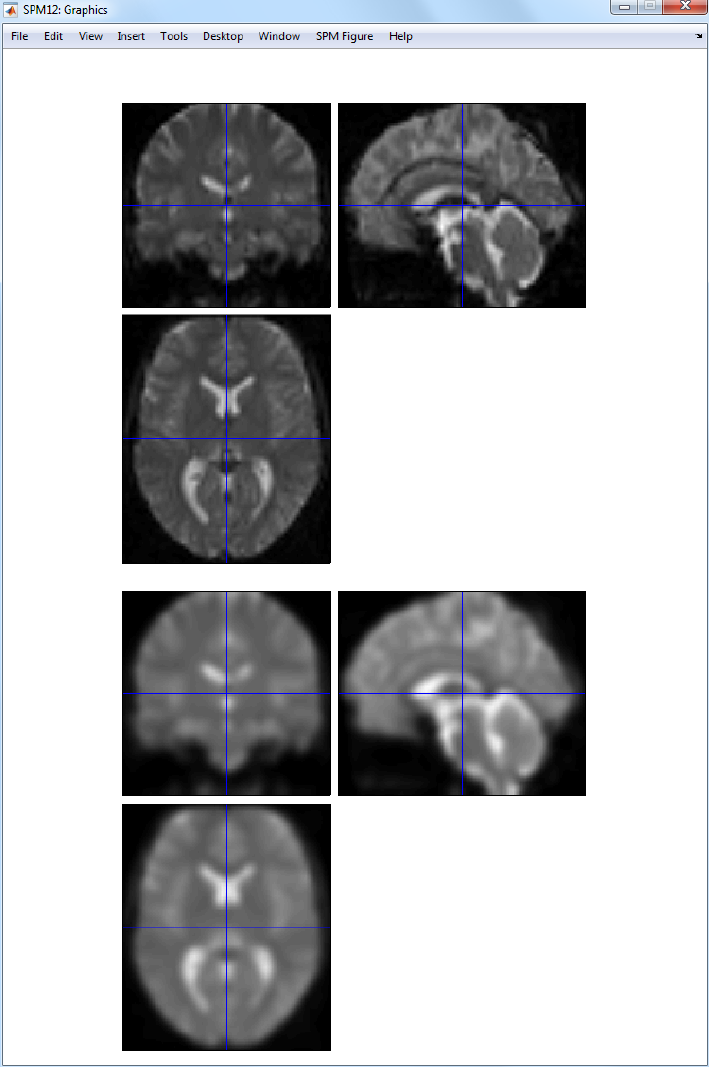

30.2 Spatial pre-processing ..................................223

30.2.1 Realignment ...................................223

30.2.2 Coregistration ..................................223

30.2.3 Segmentation ...................................223